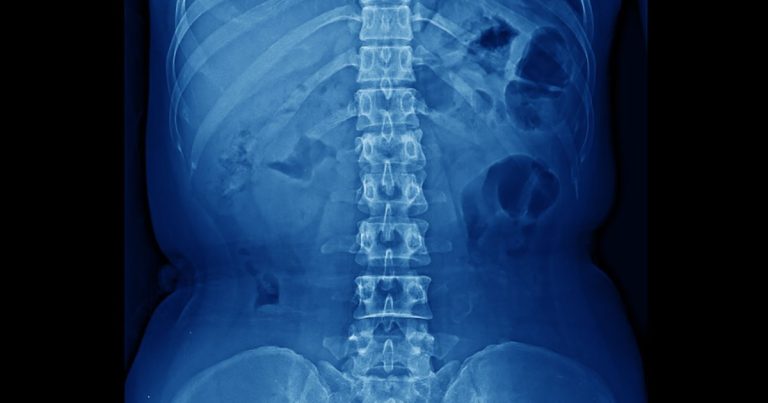

Анатомія болю в спині: що показує МРТ поперекового відділу хребта

Статті Автор: Alla Kovshova

Біль у попереку — одна з найпоширеніших причин звернення до лікаря. Він може виникати через перевантаження, малорухливий спосіб життя, травми або вікові зміни. Щоб зрозуміти точну…

Читати →

Стеноз та спондилоартроз: розшифровка вікових змін хребта

Біль у спині — одна з найпоширеніших скарг, особливо з віком. У висновках МРТ або КТ пацієнти часто бачать складні терміни: «стеноз», «спондилоартроз», «остеофіти». Вони можуть…